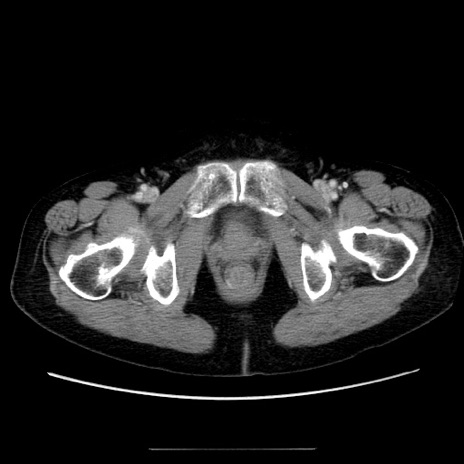

症例

冠状断像

【症例】70歳代女性

【主訴】お腹が張る

【現病歴】1週間くらい前から腹部膨満の自覚あり。昨日夜から増悪したため、本日救急外来受診。

【身体所見】意識清明、BT 36.5℃、BP 165/106mmHg、HR 80bpm、SpO2 98%、腹部:膨満、軟、自発痛・圧痛なし、触診にて不快感あり、腸蠕動音:減弱

【データ】WBC 12600、CRP 1.04